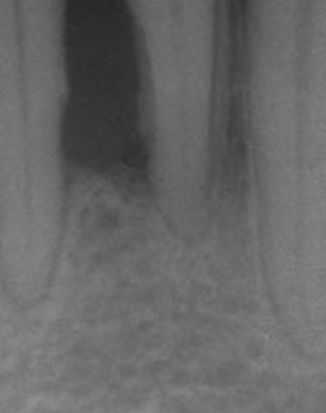

치주염(齒周炎, periodontitis, pyorrhea)은 치주 조직에 영향을 주는 염증 질환들을 의미한다. 잇몸병이 진행되면 잇몸뿐 아니라 잇몸 아래 치조골까지 파괴됩니다. 치아와 치주조직 사이의 부착소실이 일어나며, 치아가 시리고 흔들리는 증상이 나타납니다.

치주염은 치아를 둘러싸는 치조골이 점차 소실되게 하며, 치료되지 않으면 치아를 잃게 될 수도 있습니다. 치주염은 치아의 표면에 달라붙어 자라는 미생물과 이들에 대한 매우 공격적인 면역 반응에 의해 생깁니다.

치아를 지지하는 치조골이 손상되면 잇몸이 내려가고, 음식물도 예전에 비해 치아 사이에 많이 끼어 불편하며, 씹을 때 치아에 힘이 주어지지 않는 느낌이 듭니다. 이 정도 증상을 호소할 때쯤 병원에 내원하면 치료 시기를 놓쳐 치아를 뽑아야 되는 경우가 많습니다.